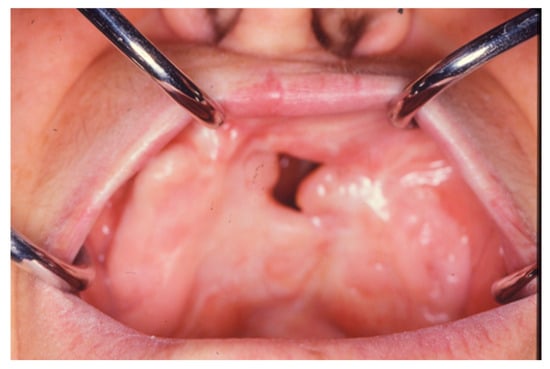

The Use of Dorsum of Tongue Flap for the Closure of an Oroantral Fistula with no Contiguous Tissue Available to Be Used: Surgical Procedure and Case Report †